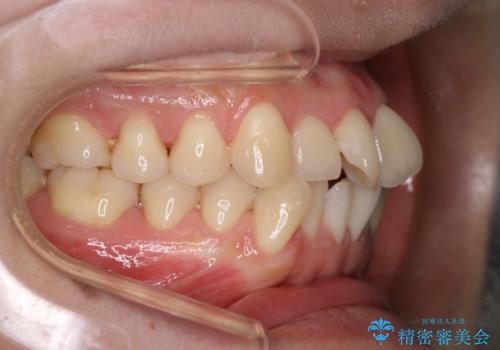

【審美装置】前歯のデコボコを綺麗に

- 上の前歯のデコボコが気になるということで来院されました。

叢生量(デコボコ)が多いため、上下左右4番目の歯を抜歯してワイヤー矯正を行う治療計画を立てました。

主訴である前歯のデコボコが改善され、噛みあわせも綺麗になりました。

歯肉退縮もなく、予定通りに治療を終えることができ良かったです。